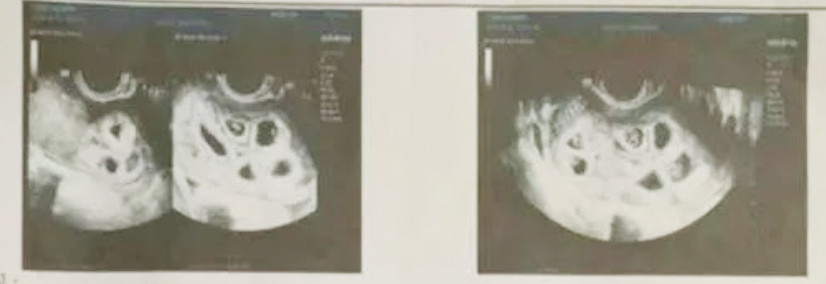

Ngày 12/11, cô đến bệnh viện kiểm tra thì thấy có tới 9 túi thai nằm sát nhau, có sự tách biệt rõ ràng. "Lúc đó, khi biết mình có thai, tôi cảm thấy rất vui mừng. Ước mơ làm mẹ của tôi đã thành hiện thực. Tôi nghĩ mình có thể sinh đôi nhưng không ngờ có 9 bào thai", cô Hầu chia sẻ.